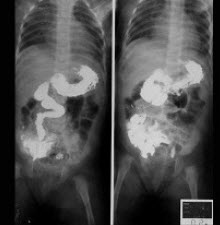

25、单项选择题

女,50岁,血便10余年,加重1年(连续出血),近2月大便时肛门常滴鲜血,量较多,X线检查如图,最可能的诊断是()

A.直肠癌

B.直肠绒毛状腺瘤

C.直肠淋巴瘤

D.直肠转移癌

E.直肠结核